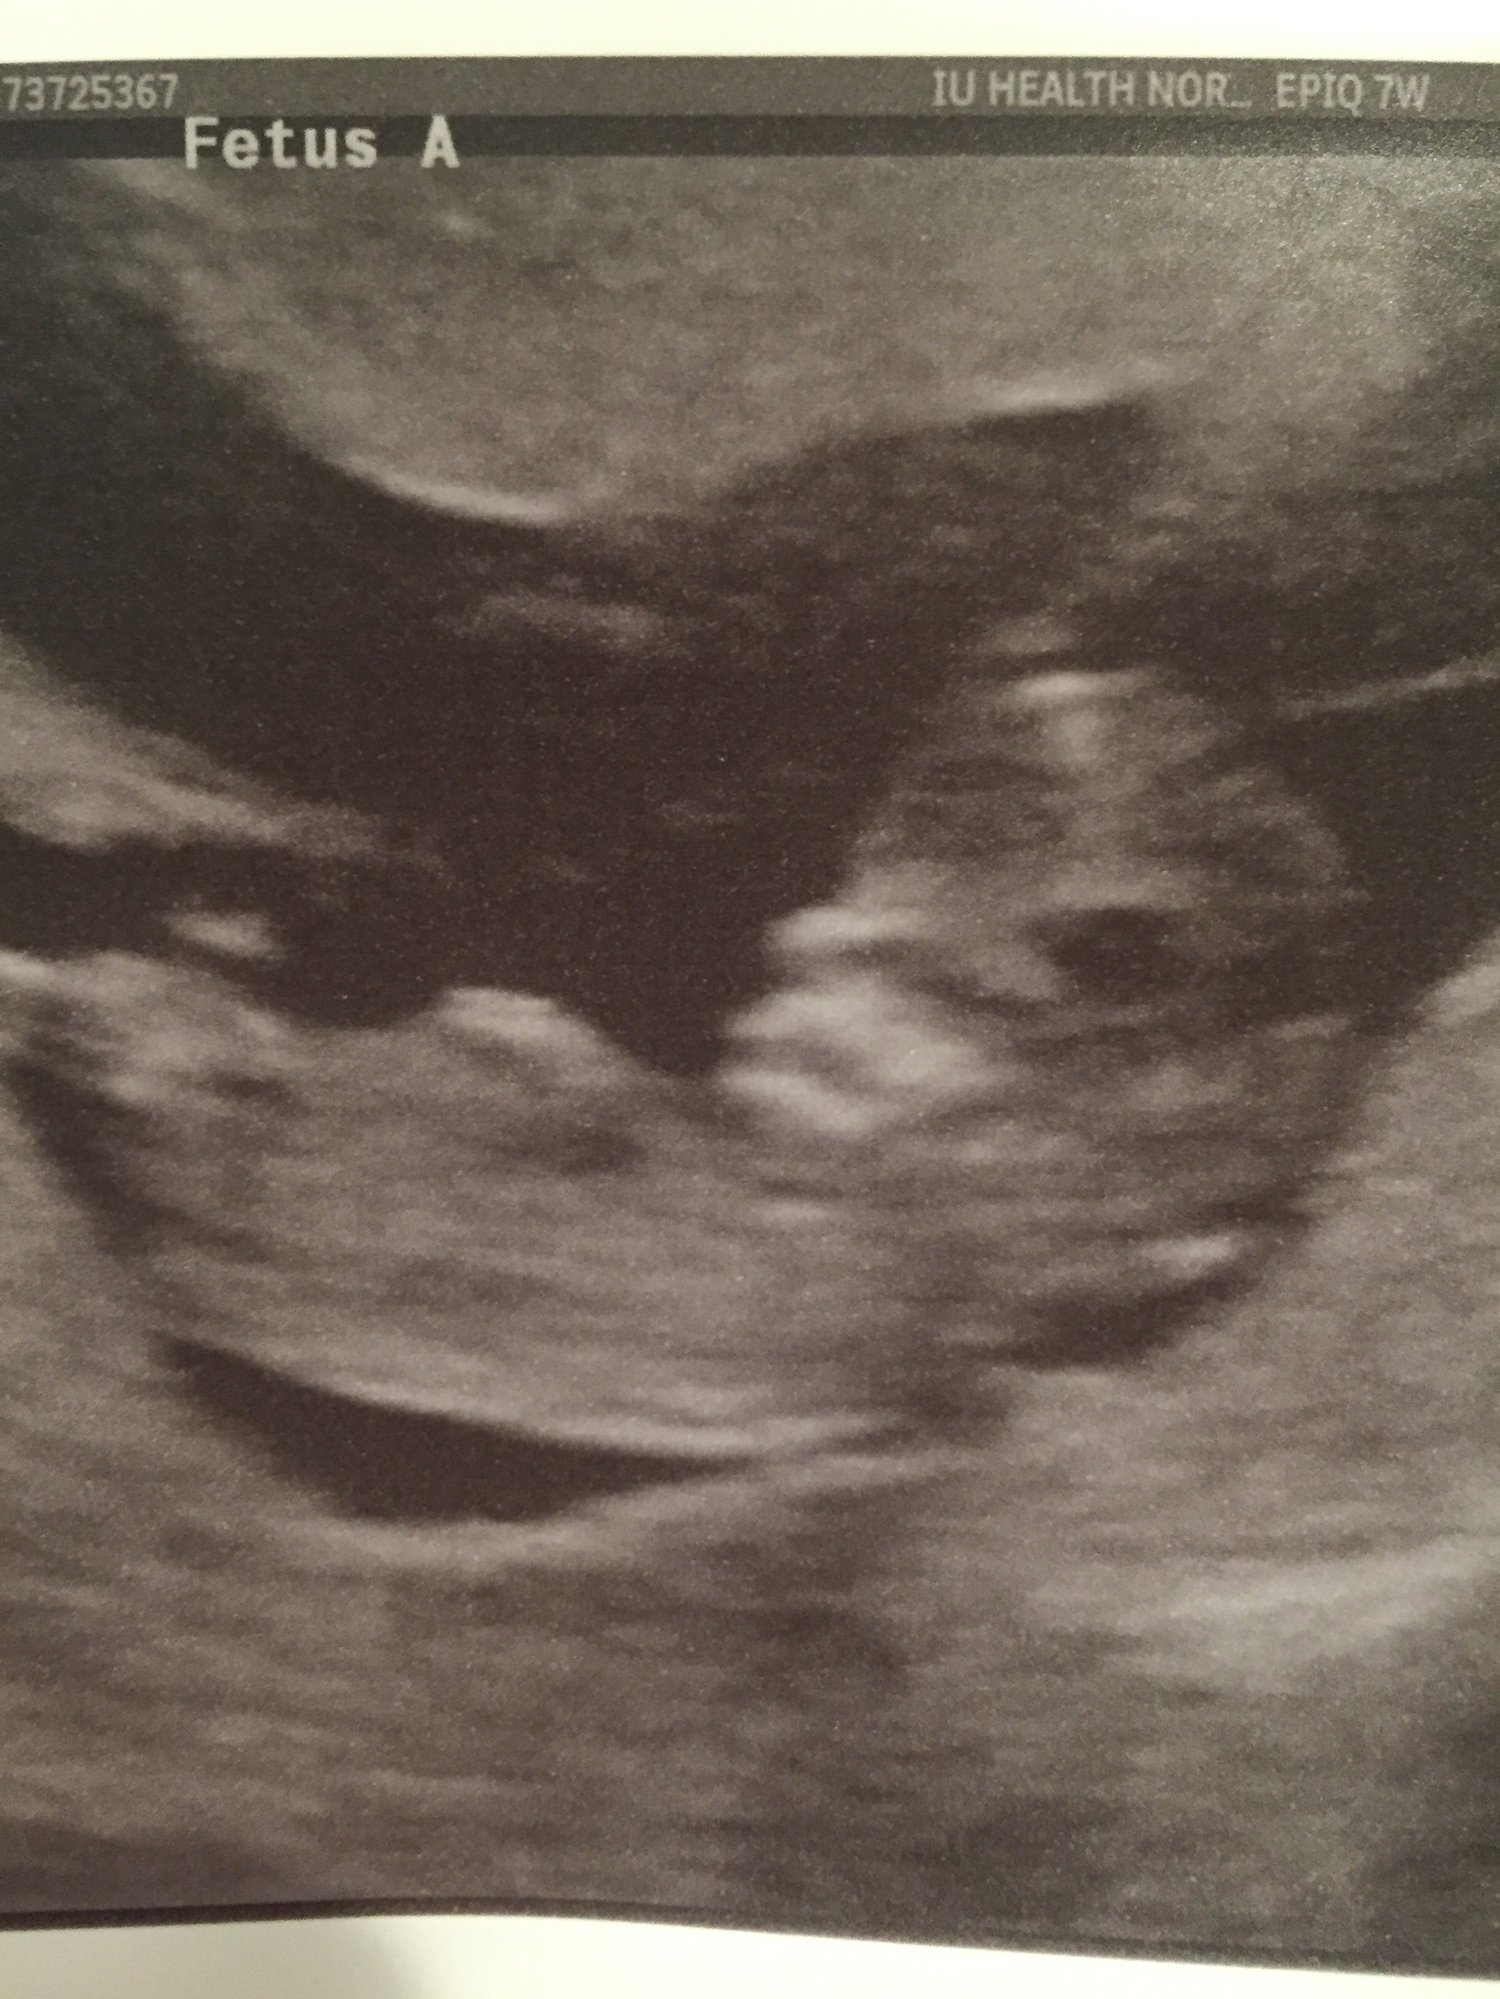

Shots from our NT scan at 12 weeks + 3 days. Measuring right on track, and the tech thought Baby B looked like a boy!

My ultrasound at 13 weeks when I went in for the NT scan! Had no idea that there are two in there !